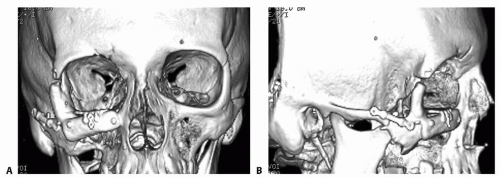

The ideal workup includes axial cuts, reformatted coronal cuts, and oblique parasagittal cuts through the orbit. 3D reformatting of the midface may also be useful (FIG 2).

![]() FIG 1 • Key anatomic points that need to be realigned and fixated: (1) Fronto-zygomatic suture; (2) Zygomatic arch; (3) Infraorbital rim; (4) Zygomatico-maxillary buttress; (5) Orbital floor. |